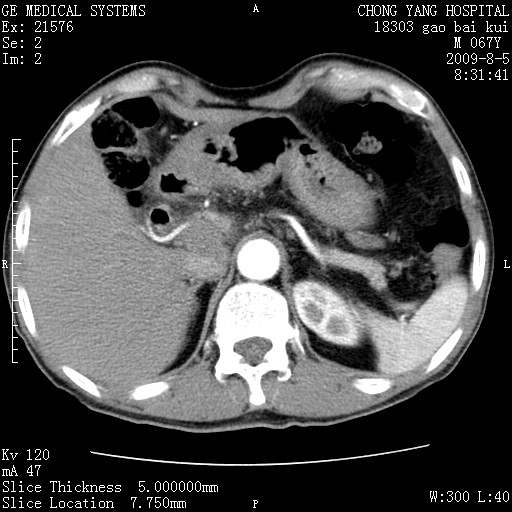

这个也过了,考虑胰腺钩突癌或壶腹癌,不除外胰管粘液乳头瘤伴胰管扩张,肝内胆管积气.

1)考虑胰头癌或壶腹癌并胰管扩张。2)肝外胆管扩张、积气,胆囊影未见;考虑术后改变。3)胃壁增厚?建议必要时行胃镜检查。

虑胰腺钩突癌或壶腹癌,不除外胰管粘液乳头瘤伴胰管扩张,肝内胆管积气.

考虑胰头癌并十二指肠受侵。